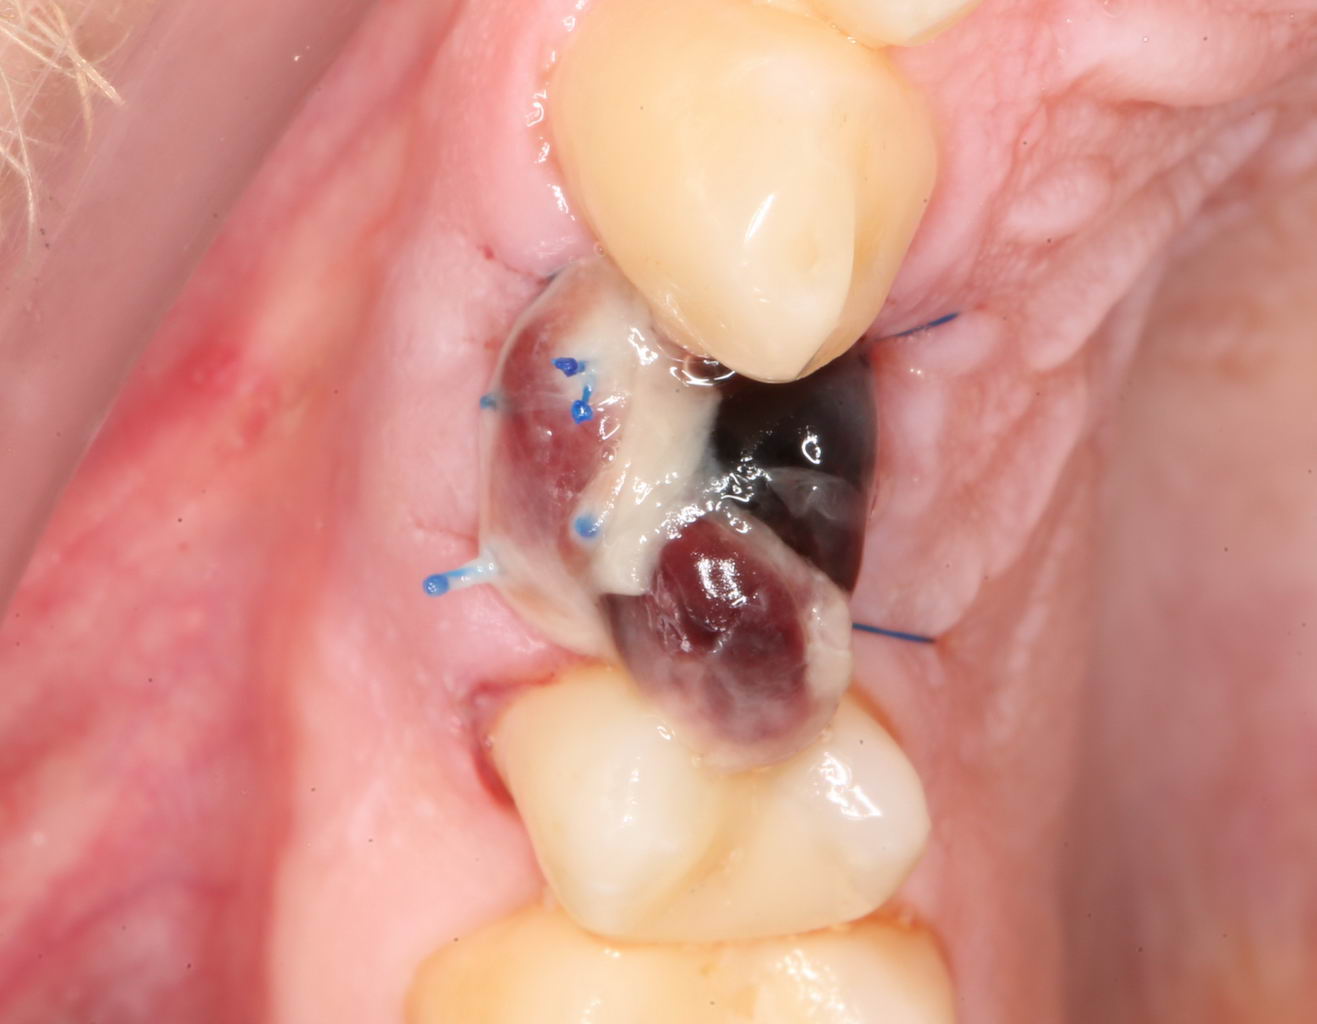

Как правило, послеоперационный период сопровождается рядом симптомов, главными из которых являются кровотечение и припухлость в области операции. К примеру, вот тот же пациент через два дня после операции:

Он полностью трудоспособен и не испытывает никакого дискомфорта. Отёков, как видите, тоже нет. Но было кровотечение. И это видно по состоянию послеоперационной раны:

На формирователе и швах повис большой кровяной сгусток. This is хорошо, поскольку он как защитная повязка, прикрывает рану от воздействия извне. Возможно, именно этим объясняется отсутствие каких-то неприятных симптомов в послеоперационном периоде.